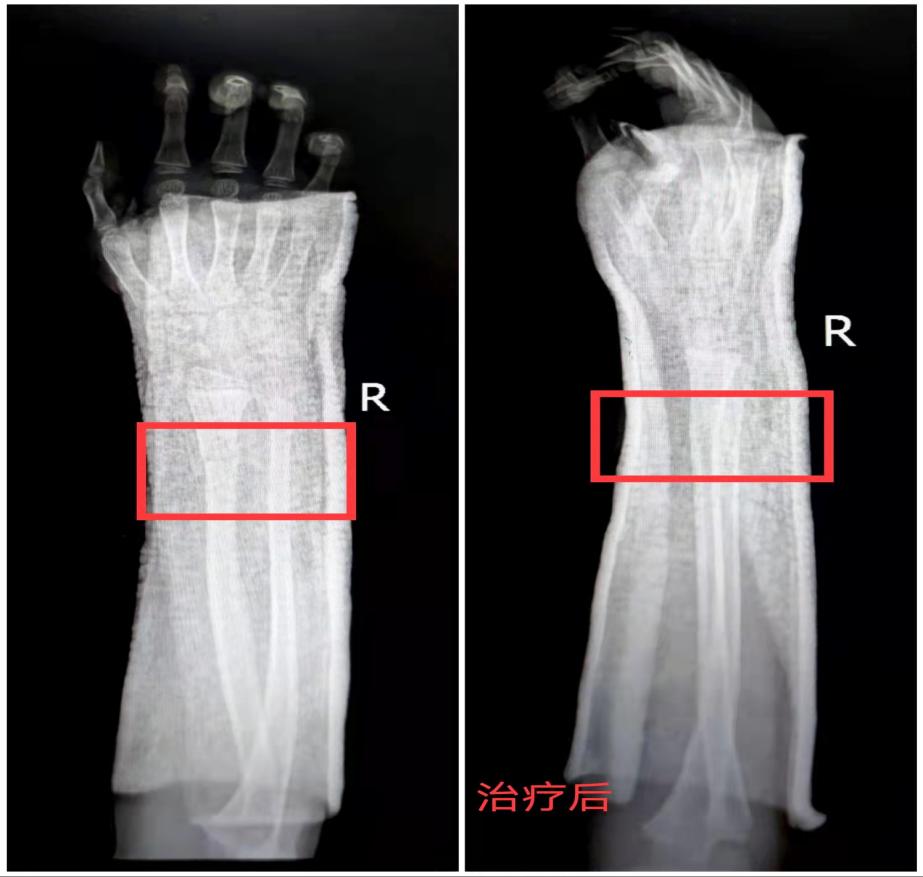

x线检查的结果显示孩子确实是骨折了,还有轻微的移位。当得知孩子的确是骨折之后孩子的妈妈又开始变得焦虑不安,紧张地问刘医生:“大夫,孩子的手会不会受到影响?这个骨头能不能自己长好啊?”刘医生告诉孩子的妈妈,孩子的骨头愈合能力特别强,只要把移位的地方对好,之后骨头就能慢慢愈合,对手的功能也不会有任何影响。然后,耐心向孩子妈妈讲解了治疗方案,征得孩子妈妈同意后,在孩子骨折的部位打上了石膏,固定好之后又拍了个片子看看复位的效果。

这整个过程孩子都很配合,刘医生还不忘逗小姑娘,说她像铁臂阿童木,还告诉她,这样一点也不会影响她回家后画画。

最后还嘱咐孩子的妈妈,回家后要观察孩子胳膊疼痛的情况有没有好转;看看手指的活动的情况,有没有肿胀、颜色和好手(左手)是不是一致;适当进行握拳和伸指锻炼,以防关节因为长时间不动变僵硬;一周之后来门诊复查石膏松紧的情况,六周可以再复查骨折愈合情况,顺利的情况下6-8周就可以去掉石膏了。